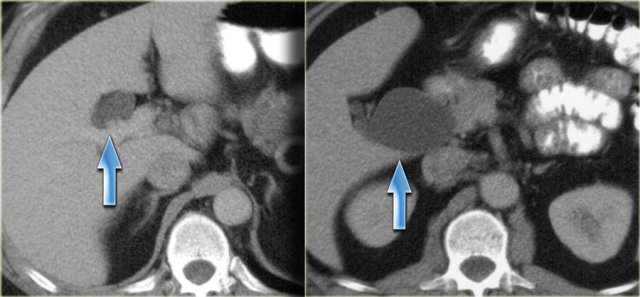

On the left a patient with more pronounced CT findings.

Study the image and then continue reading.

The findings are:

- Discontinuous dilatation

- Bile wall thickening at the level of the porta hepatis

- Lymphadenopathy